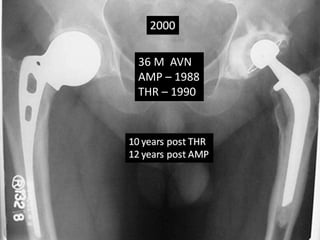

36 M AVN AMP – 1988 THR – 1990

Case summary •36 yrs Male had Bilateral AVN hips • AMP done in 1988 rt side at the age of 36 yrs • Triad - cemented THR was done on left side in 1990 at the age of 38 yrs. • Advised revision of cup due to poly wear 2005 • Met with Road traffic accident in June 2007.